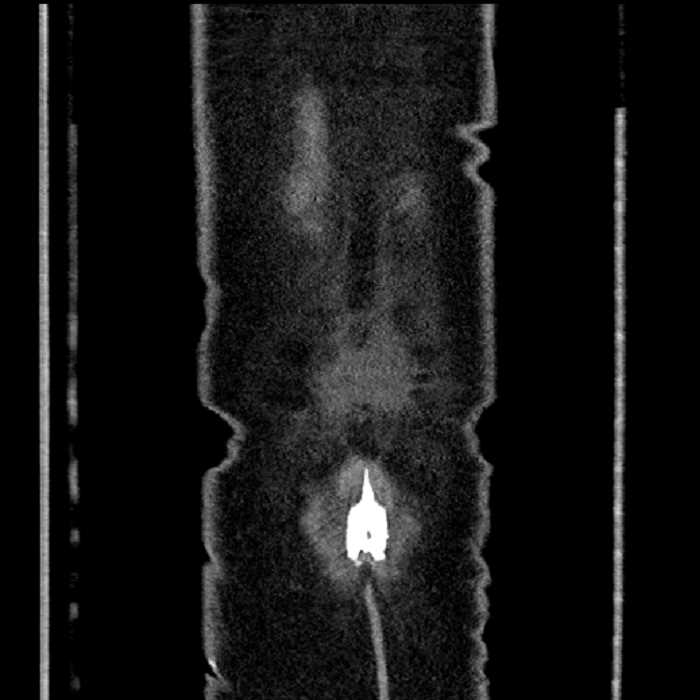

• Mild mural thickening of a segment of the sigmoid colon with adjacent fat stranding and a 1.5 cm fluid and gas collection along the tip of an inflamed diverticulum

• Loss of the normal fat plane between this collection and adjacent loops of small bowel, which demonstrate mural thickening

• Ankylosis of both sacroiliac joints

Hepatic abscess showing the double target sign with low density internally surrounded by a thin inner enhancing rim (red arrow) and ill-defined outer low density rim (yellow arrow). Blue arrow indicates an internal septation. Red arrows: additional smaller subcapsular abscesses. Red arrow: focal contained perforation associated with diverticulitis.